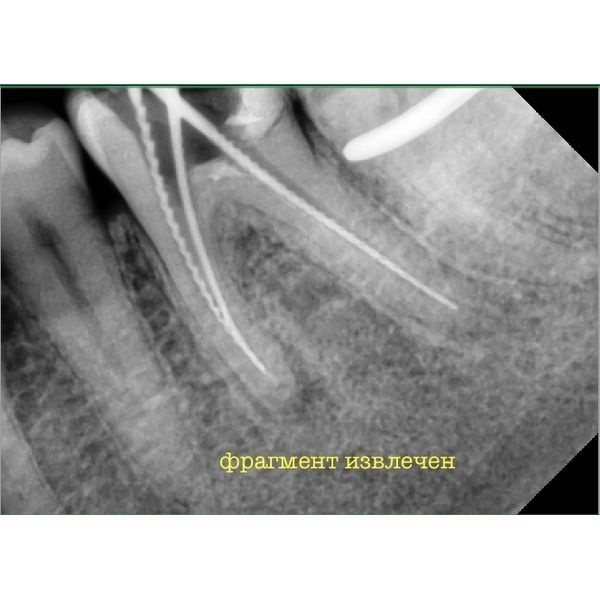

Уже после первой процедуры все симптомы прошли. Следующее посещение назначили через 2 недели, 16 ноября. Пациенту извлекли второй фрагмент и запломбировали каналы с использованием гуттаперчи.

По окончании лечения новых жалоб у мужчины не было. Его направили на восстановление зуба под коронку и дальнейшее протезирование.